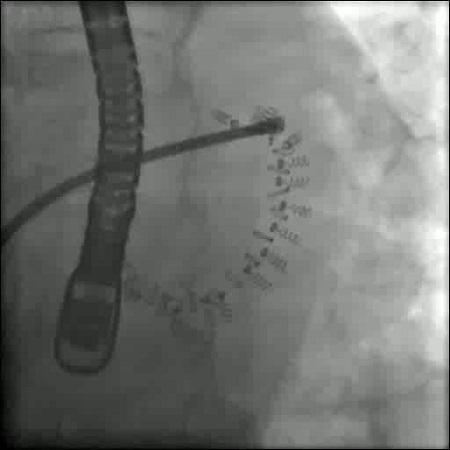

Premiere in Österreich: Herzklappenring‐Implantation ohne Eröffnung des Brustkorbes

Erstmals in Österreich wurde im Dezember 2017 am Klinikum Wels‐Grieskirchen ein künstlicher Herzklappenring minimal‐invasiv ohne Eröffnung des Brustkorbes bei einer Patientin implantiert. Innovative kardiologische Interventionen ermöglichen heute mittels Kathetertechnik schonende und wirksame Behandlungen am schlagenden Herzen.

mehr: Premiere in Österreich: Herzklappenring‐Implantation ohne Eröffnung des Brustkorbes